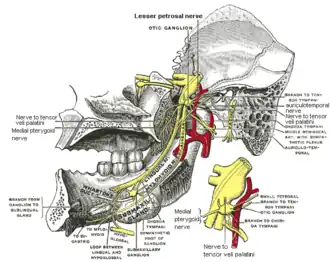

Distribution of the maxillary and mandibular nerves, and the submaxillary ganglion. (Inferior alveolar visible at center left.) | |

Mandibular division of the trigeminal nerve. (Inferior alveolar labeled at bottom right.) | |